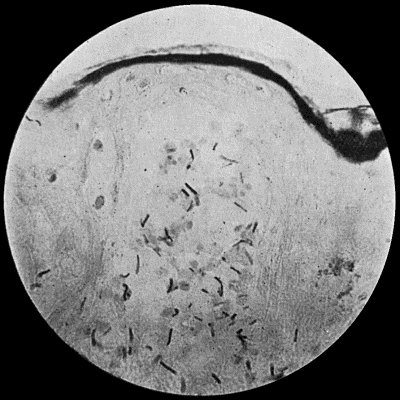

Fig. 4.—Bacillus coli communis in Urine, from a case of Cystitis. × 1000 diam. Leishman's stain.

Bacillus Coli Communis.—This organism, which is a normal inhabitant of the intestinal tract, shows a great tendency to invade any organ or tissue whose vitality is lowered. It is causatively associated with such conditions as peritonitis and peritoneal suppuration resulting from strangulated hernia, appendicitis, or perforation in any part of the alimentary canal. In cystitis, pyelitis, abscess of the kidney, suppuration in the bile-ducts or liver, and in many other abdominal conditions, it plays a most important part. The discharge from wounds infected by this organism has usually a fœtid, or even a fæcal odour, and often contains gases resulting from putrefaction.

It is a small rod-shaped organism with short flagellæ, which render it motile (Fig. 4). It closely resembles the typhoid bacillus, but is distinguished from it by its behaviour in artificial culture media.